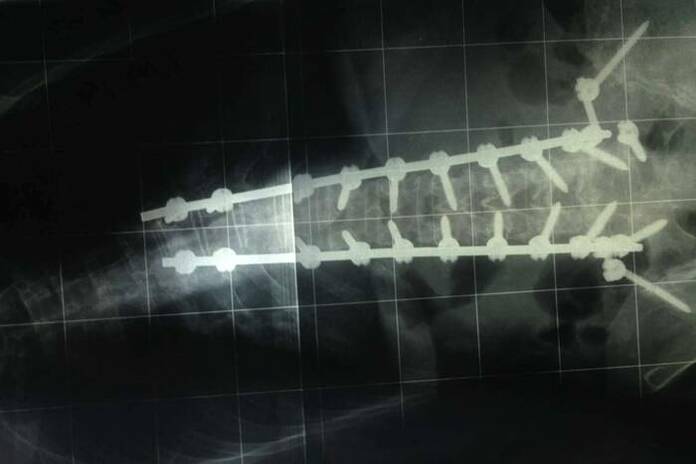

En caso de que el síndrome se deba a inestabilidad de la columna, se debe realizar una fusión espinal para unir las vértebras adyacentes con la finalidad de preservar la resistencia de la columna. Hoy en día, existen técnicas mínimamente invasivas con el objetivo de disminuir el trauma de la intervención quirúrgica y así acelerar la recuperación del paciente.